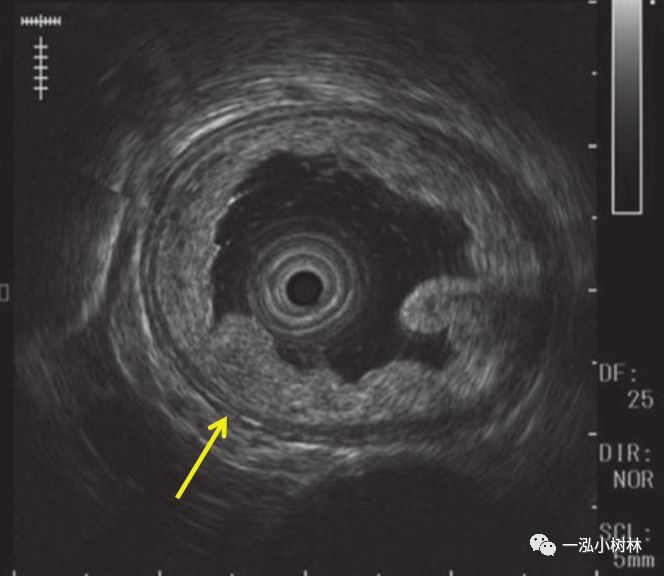

图3 超声内镜:与病灶隆起部分一致的第三层变薄,被认为浸润深度已达到T1b-SM2。最后,我们诊断为Barrett食管腺癌并侵犯SM2,并进行手术治疗。